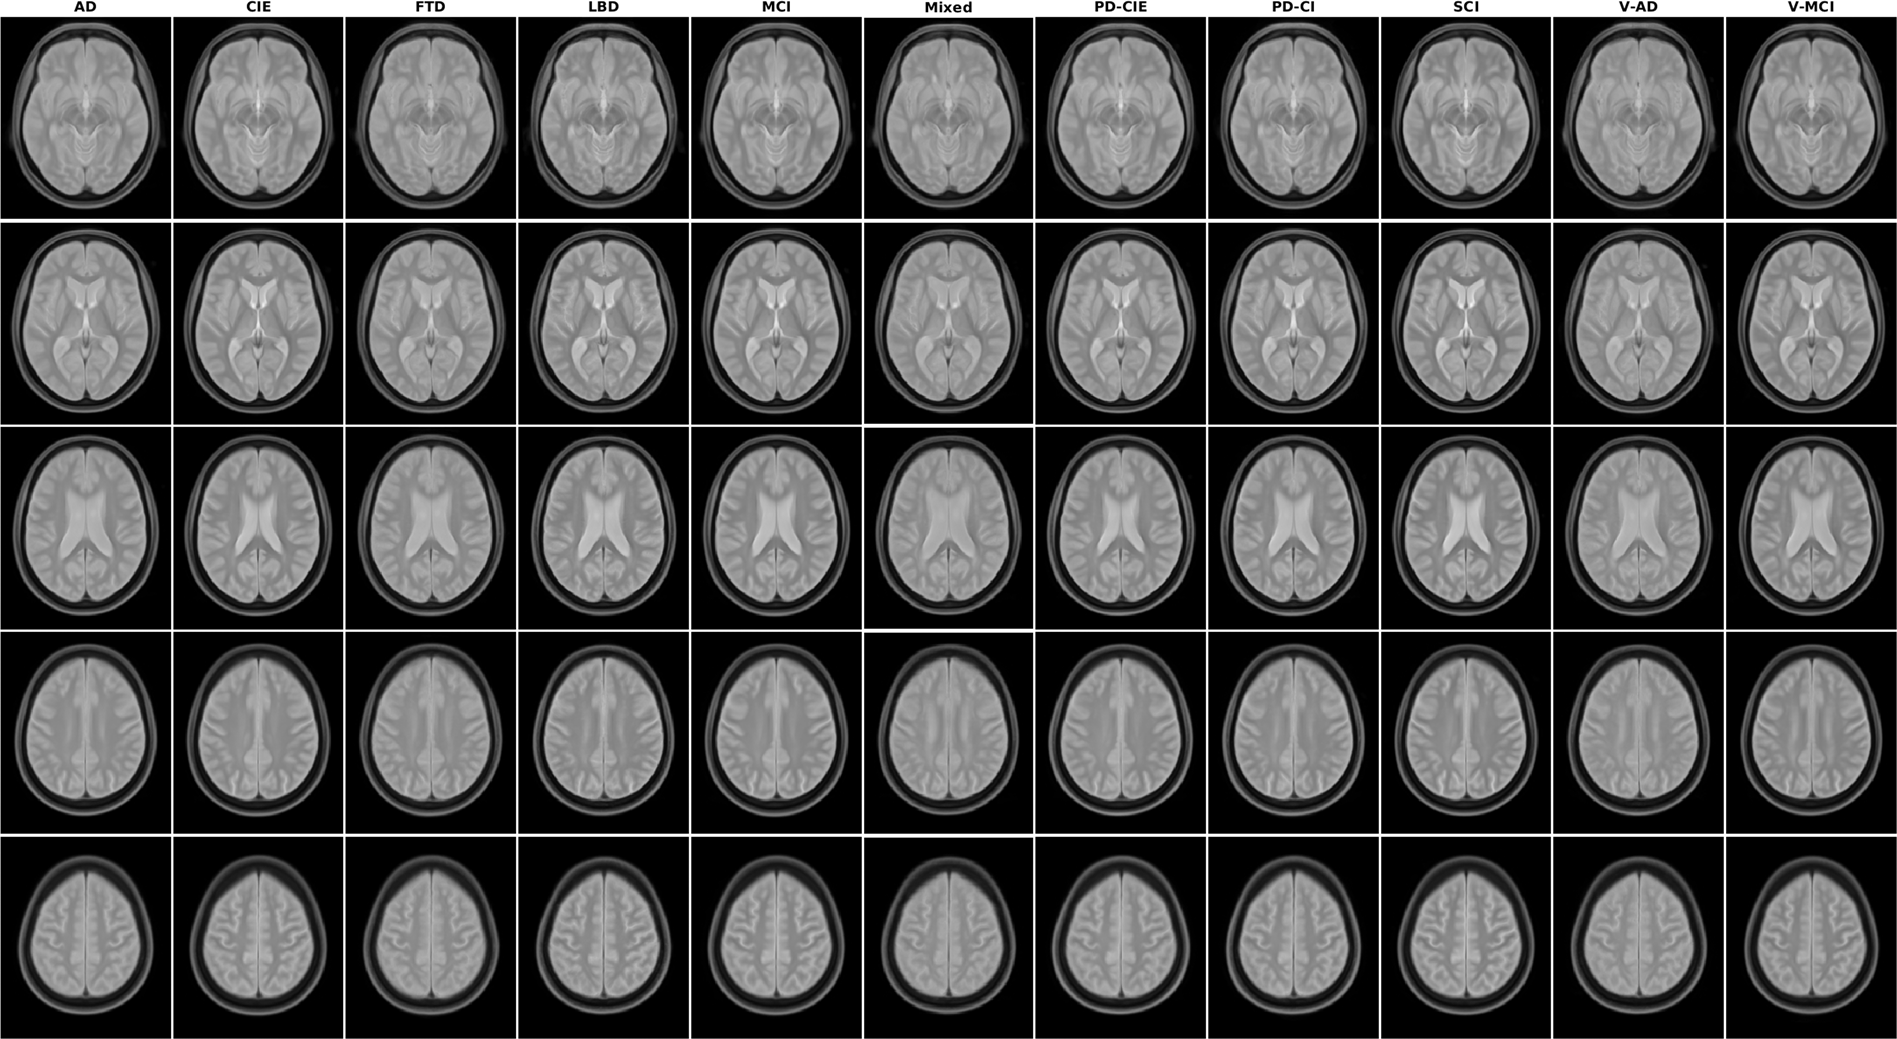

Axial slices of PD average templates for all diagnostic groups.